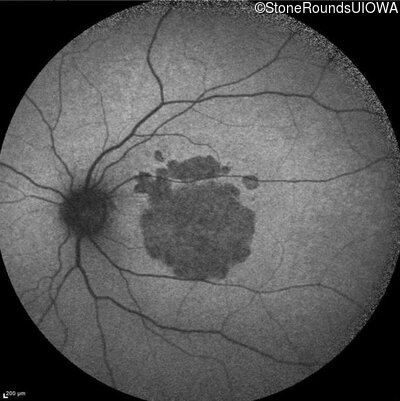

Infrared Fundus Photograph - Right - 20/63

Exemplar